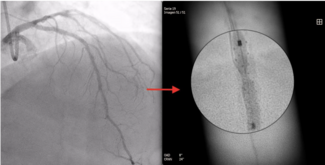

Konstantinos Filippou, MD; Konstantinos Manousopoulos, MD, PhD; Panagiotis Varelas, MD; Dimitrios Karelas, MD; Ioannis Papadopoulos, MD; Ioannis Tsiafoutis, MD, PhD

The authors report a rare case involving fenestration of a malpositioned coronary stent that was previously deployed at the ostium of the right coronary artery.